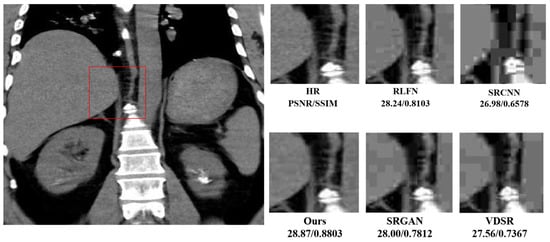

| SRCNN | 57 | 1.90 | 27.78/0.7120 | 28.45/0.7276 | |

| RFDN [36] | 550 | 20.40 | 28.12/0.8023 | 29.23/0.7453 | |

| Baseline | 543 | 16.41 | 28.34/0.8230 | 29.37/0.7478 | |

| Ours | 468 | 13.23 | 28.46/0.8256 | 29.48/0.7513 |